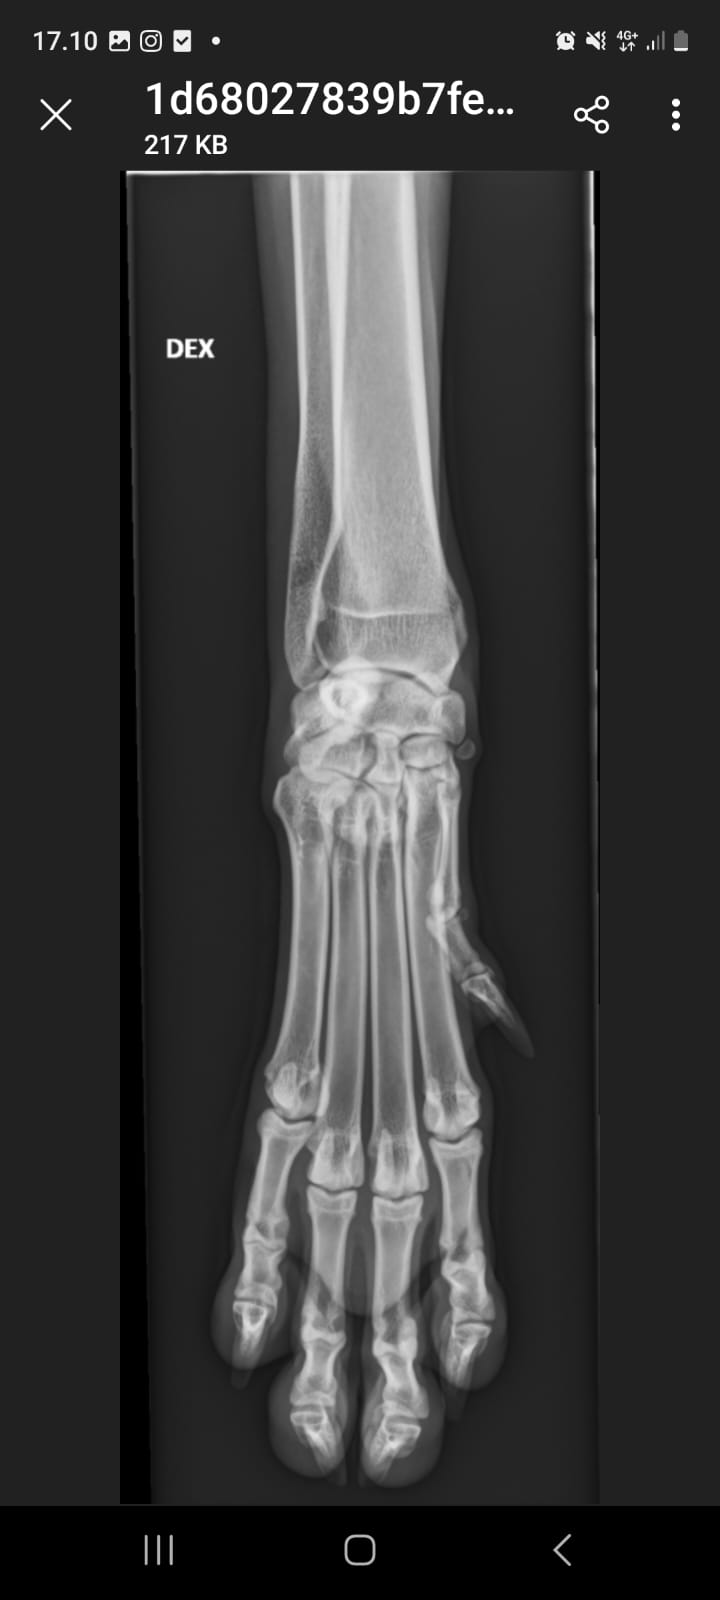

- Kasvuajan luustosairaus (HOD) ilmenee verenvuotona ja kalkkeutumina aivan luukalvojen alla, varsinkin ranteiden yläpuolella. Ulospäin sairaus näkyy lämpimänä turvotuksena kyynärluiden ja värttinäluiden alaosassa eli ranteiden yläpuolella. Koira aristaa usein jalkojaan, ontuu, pahimmassa tapauksessa koira ei pysty edes seisomaan. Sairauteen liittyy useasti kuume ja yleiskunnon heikkeneminen. Tämä sairaus on tyypillinen nimenomaan suurille, nopeakasvuisille roduille, yleinen esiintymisikä 3-6 kk. Muutokset näkyvät röntgenkuvissa selvästi.

- Voimalla HOD oireili ranteissa. Ranteet kuvattiin ja sieltä tyypillinen tulehduksellinen löytö. Hoitona oli kipulääke-kuuri sekä antibiootti. HOD ei ole perinnöllinen. Näin kriittisessä kasvuvaiheessa oleva HOD on voinut kuitenkin vaurioittaa tulehtuneen nivelen nivelpintaa ja näin ollen aiheuttaa kasvuhäiriön.

- ranteet kuvattu terveiksi 08/25!